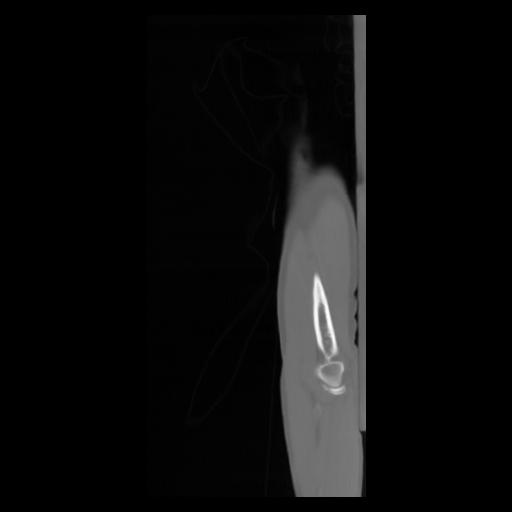

30 CUERPO,CE,Sagittal,3.000,CUERPO,Sagittal,